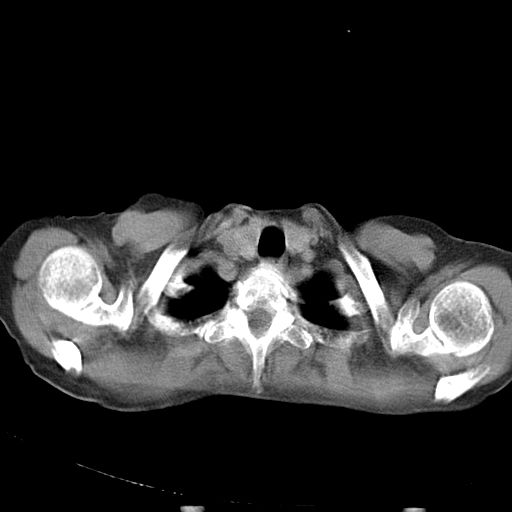

以下是引用dyqct在2006-12-7 21:08:00的发言:[br]考虑:1、肝内外胆管多发性结石伴肝左叶外侧段肝萎缩;[br] 2、右膈下多发脓肿;[br] 3、右侧少量胸腔积液、斜裂积液;[br] 4、左肾囊肿。

以下是引用jiazh在2006-12-7 20:37:00的发言:[br]肝脏周围半狐形低密度影,肝脏表面受压推移,考虑膈下脓肿可能性大;2、右侧胸腔积液

以下是引用拾荒者在2006-12-7 21:44:00的发言:[br]肝内外胆管多发结石,右膈下多发脓肿,右胸膜腔及叶间裂积液,左肾囊肿。[br] [br]